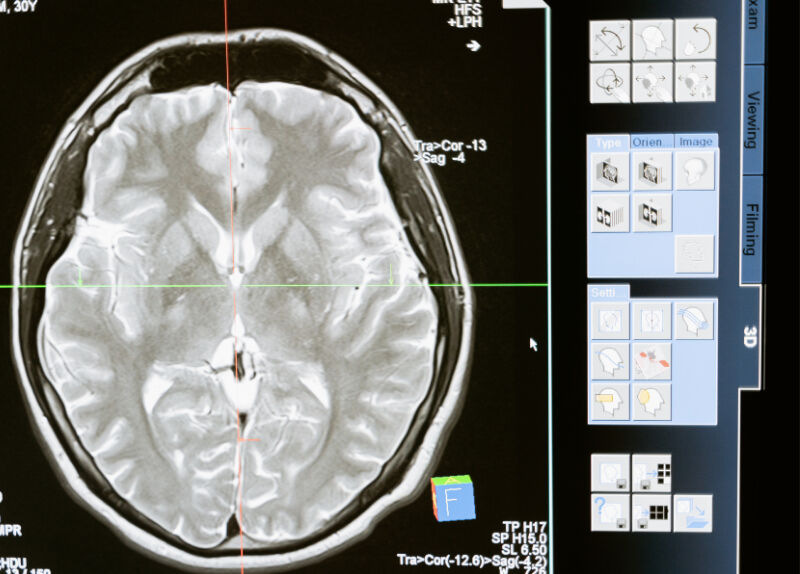

Hastalığa dair bilgiler aktaran Doç. Dr. Emre Gölboyu, “Hastamızın ağrıları ilaç tedavisine rağmen iyileşmiyordu. Bu hastalık, hastanın yüzünün bir tarafında, ‘şimşek çakması' gibi ağrılar olarak kendini gösterir. Hastalık, kısa süren ancak hayatı zindan eden, yemek yemesini, diş fırçalamasını engelleyebilecek düzeydedir. Hastaların kilo vermesini, bazen yanlışlıkla bütün dişlerinin çekilmesine kadar sebep olabilecek kronik bir hastalık” dedi.

Doç. Dr. Gölboyu, uygulanan tedaviye yönelik yaptığı açıklamada, “En başta hastanın yaşını dikkate alıyoruz. Eğer çok genç yaştaysa ya da bunun sebebi bir MS hastalığıysa, böyle hastalarda daha çok ‘gamma knife' tedavisi öneriyoruz. Ancak cerrahi süreci kaldıramayacak ya da yaşı ileri hastalarda Algoloji tarafından yapılan radyo frekans yöntemlerini öneriyoruz. Biz de kliniğimizde günübirlik işlem şeklinde, floroskopi denilen röntgen makinesi kullanarak buradaki sinirlere ulaşıyoruz ve bu sinirleri geçici bir süre yakıyoruz. Bu sayede hastalarımız yaklaşık 2-3 yıl kadar, ağırlığında azalma, günlük işlerinde ve hayat kalitesinde artış, kilo alma, yemek yerken daha rahat etme gibi dönüşlerle bize gelmekteler” diye vurguladı.